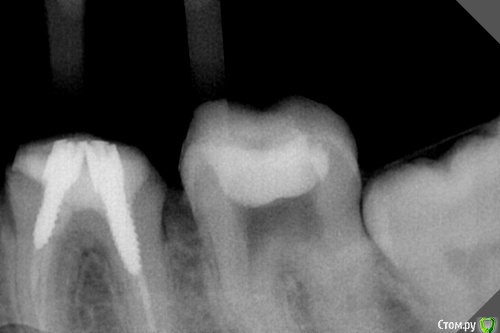

dr.Dre Опубликовано 27 мая, 2016 Поделиться Опубликовано 27 мая, 2016 Добрый день коллеги,дайте пожалуста совет ,никак не могу разработать медиальные устья и это уже не первый зуб что я делаю не так Ссылка на комментарий

pils Опубликовано 27 мая, 2016 Поделиться Опубликовано 27 мая, 2016 Может расскажите сначала, что Вы делаете? На снимке каналы видны очень и очень четко. Никаких проблем быть не должно. 1 Ссылка на комментарий

dr.Dre Опубликовано 27 мая, 2016 Автор Поделиться Опубликовано 27 мая, 2016 (изменено) Может расскажите сначала, что Вы делаете? На снимке каналы видны очень и очень четко. Никаких проблем быть не должноДелаю доступ заливаю все гипохлоритом и лимонкой,потом С pilot 8 и все далее ничего не виходит ,не цепляет ,пробывал ультразвуком больше боюсь что б не разбить сильно зуб. Изменено 27 мая, 2016 пользователем dr.Dre Ссылка на комментарий

pils Опубликовано 27 мая, 2016 Поделиться Опубликовано 27 мая, 2016 На снимке каналы видны абсолютно четко. Единственное, что приходит в голову, и об этом коллеги Вам писали в другой теме, так это неправильный угол... 2 Ссылка на комментарий

Ker Опубликовано 28 мая, 2016 Поделиться Опубликовано 28 мая, 2016 Может опилками забиваете, можете уступ нарезаете, да много чего может быть. Глазами то хоть видно устья? Ссылка на комментарий

dr.Dre Опубликовано 29 мая, 2016 Автор Поделиться Опубликовано 29 мая, 2016 Может опилками забиваете, можете уступ нарезаете, да много чего может быть. Глазами то хоть видно устья?да видно Ссылка на комментарий